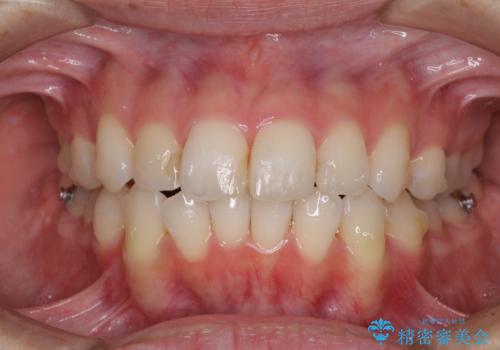

- 前歯のデコボコを気にして来院された患者様です。

主に下顎歯列全体の後方移動とIPR(歯と歯の間を削る)によってデコボコが解消するように設計し、インビザラインにより治療を行うこととしました。

舌突出癖がある方ですと、叢生が解消すると同時に前方に拡大されてしまいますが、ゴムかけをしっかりと行ってくださったこともあり、スッキリとした仕上がりとなりました。